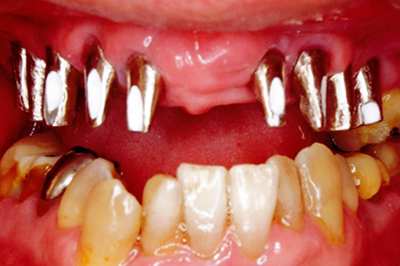

治療例2

歯ぐきが安定した状態

土台をたてた

噛める機能を回復